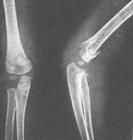

受傷後,局部腫脹,疼痛,肘後吐起,皮下淤斑。檢查可發現肘上方壓痛,後方可捫到骨折端,X線拍片可發現骨折的存在及典型的骨折移位,即近折端向後下移位,遠折端向前移位,骨折線呈由前上斜向後下的斜形骨折。由於肘後方軟組織較少,折端銳利,可刺破皮膚形成開放骨折,由於暴力作用的方向及跌倒時的體位改變,骨折可出現尺側或蹺側移位。少有合併神經血管損傷。

受傷後,局部腫脹,疼痛,肘後吐起,皮下淤斑。檢查可發現肘上方壓痛,後方可捫到骨折端,X線拍片可發現骨折的存在及典型的骨折移位,即近折端向後下移位,遠折端向前移位,骨折線呈由前上斜向後下的斜形骨折。由於肘後方軟組織較少,折端銳利,可刺破皮膚形成開放骨折,由於暴力作用的方向及跌倒時的體位改變,骨折可出現尺側或蹺側移位。少有合併神經血管損傷。 治療的基本原則與伸直型肱骨髁上骨折相同,但手法復位的方向相反,在肘關節屈曲40度左右行外固定,4~6周后開始主動練習肘關節屈伸活動。 兒童期肱骨髁上骨折復位時,橈側或尺側移位未得到糾正,或合併了骨骺損傷,骨折癒合後,可出現肘內、外翻畸形。不嚴重的畸形可在兒童生長發育過程中逐漸得到糾正,經過觀察,畸形有加重的趨勢,合併有功能障礙者,在12~14歲時,可作肱骨下端截骨矯正術。術中注意橈神經和尺神經的牽拉損傷,可先解剖神經,再作截骨矯正術。